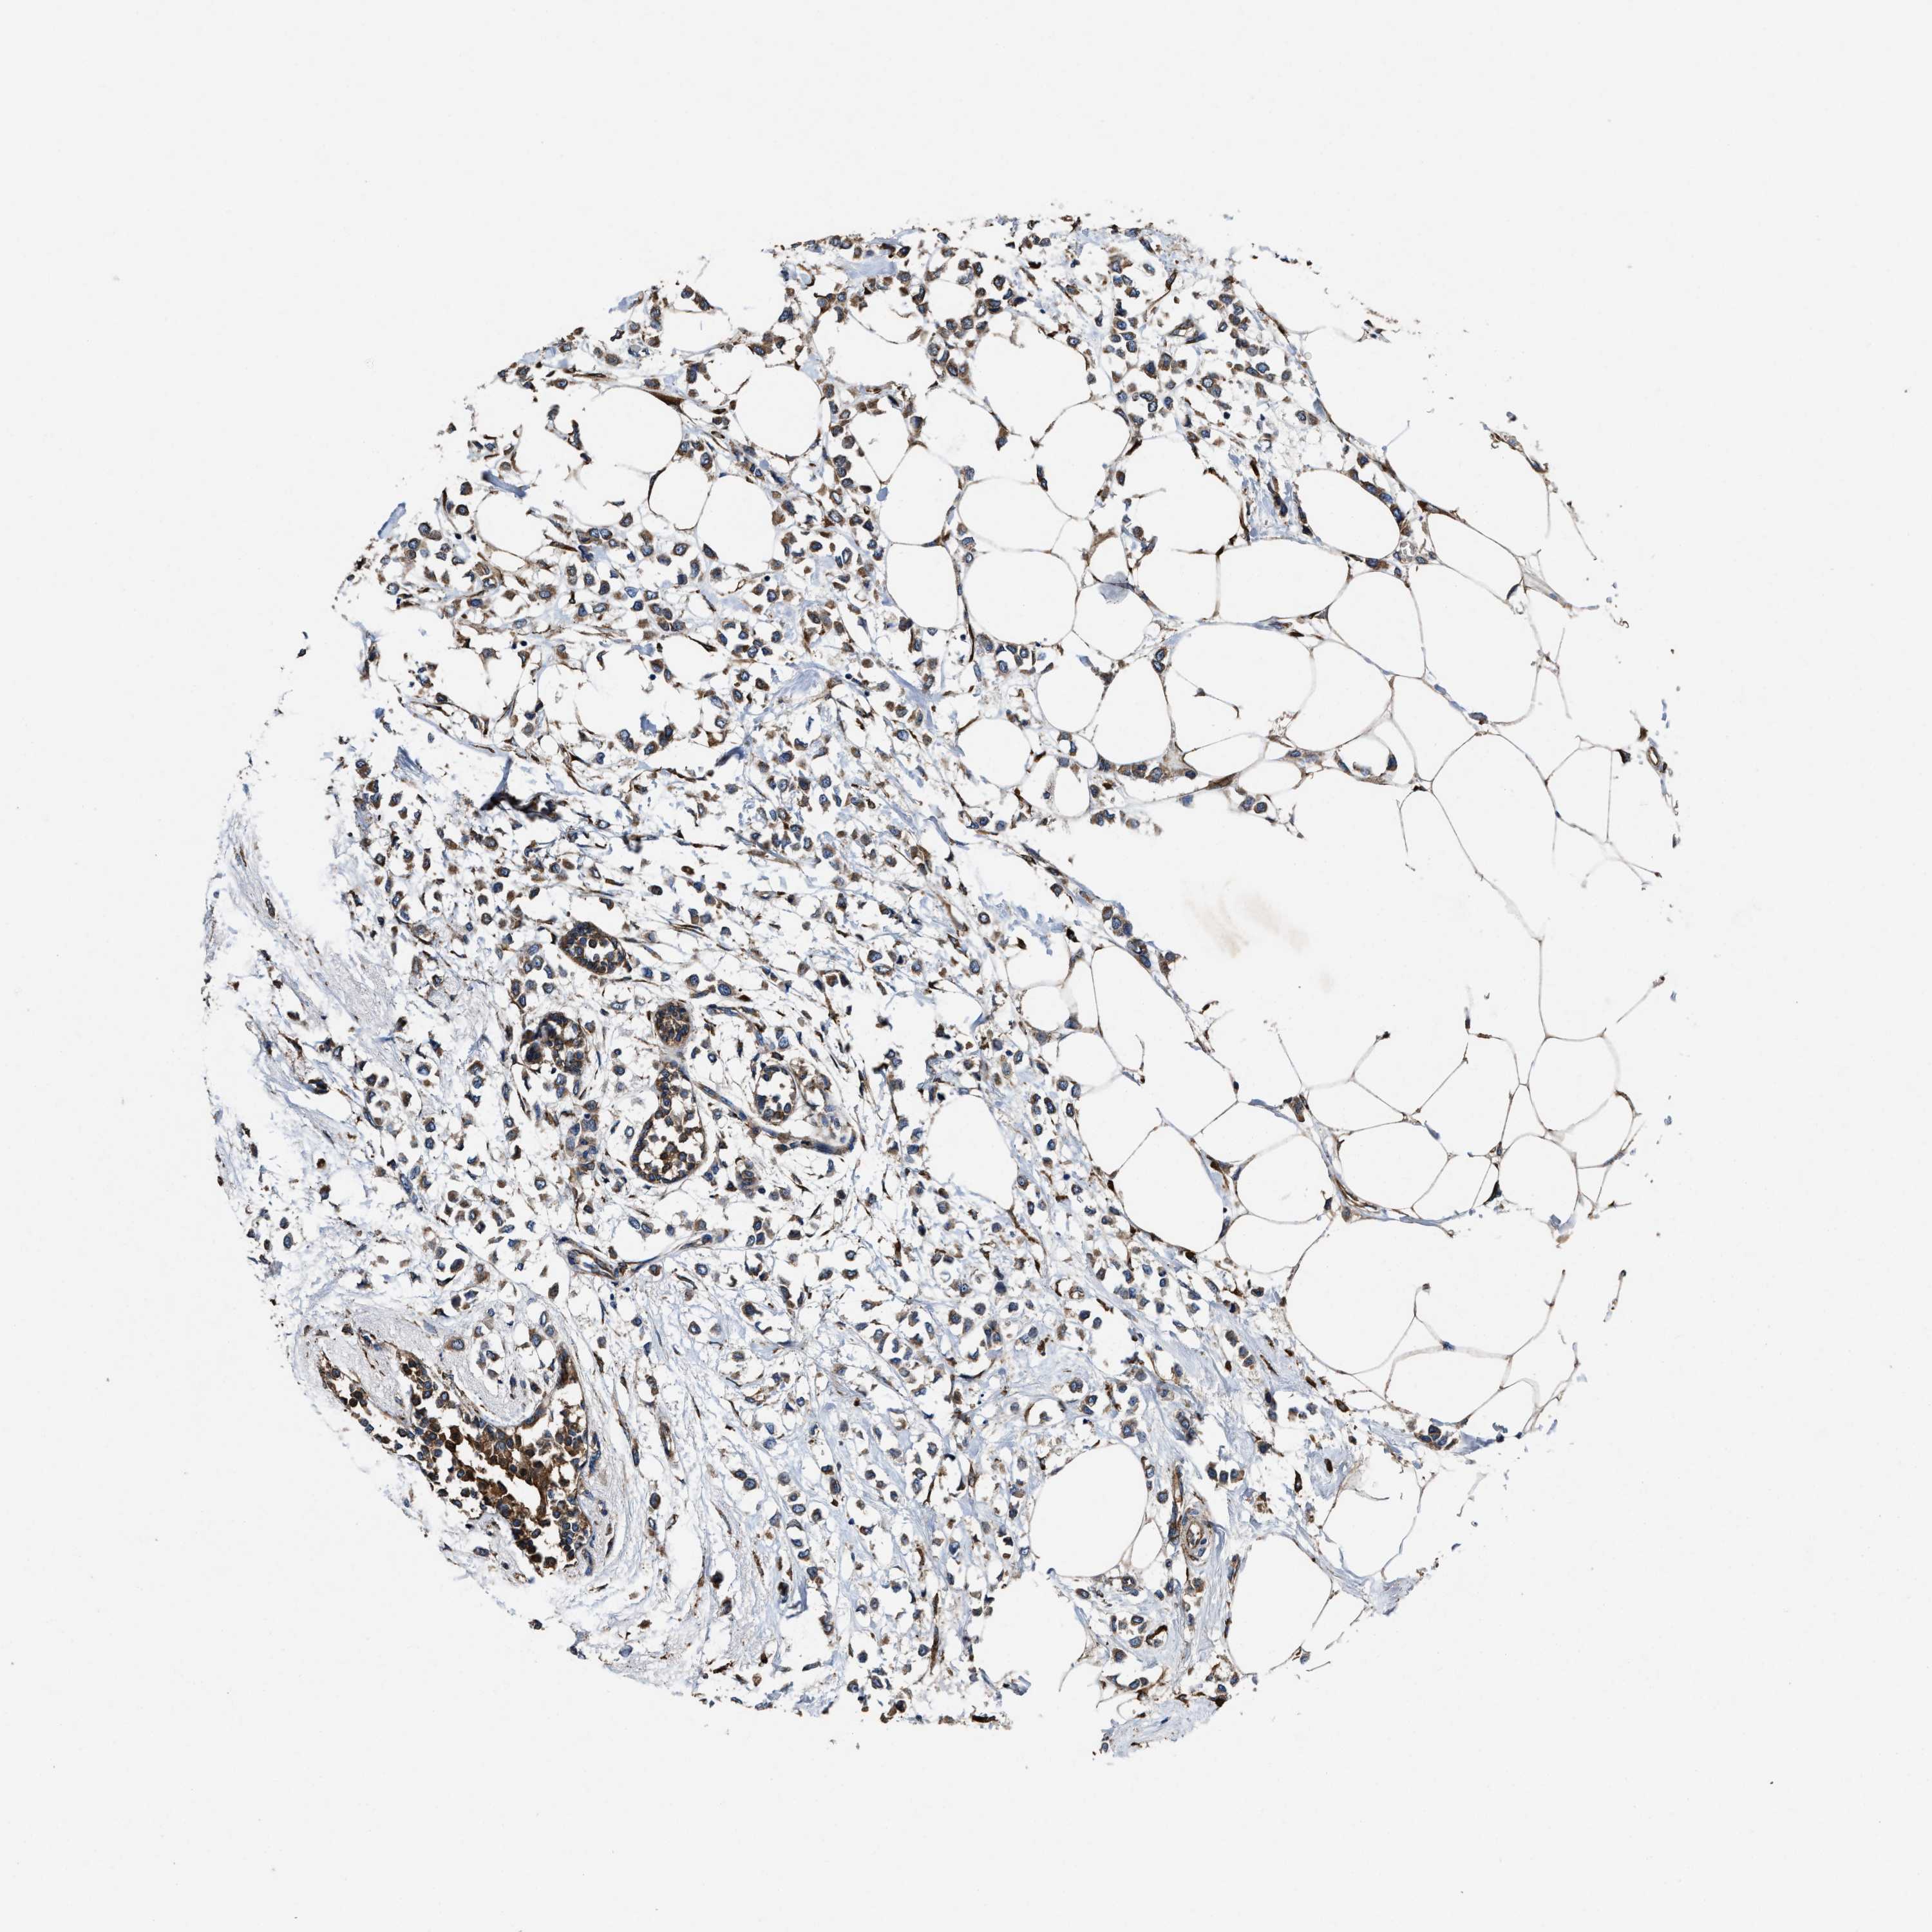

CANCER BREAST CANCER Show tissue menu

BRCA TCGA BRCA VALIDATION PROTEIN EXPRESSION

Breast cancer

Human cancer